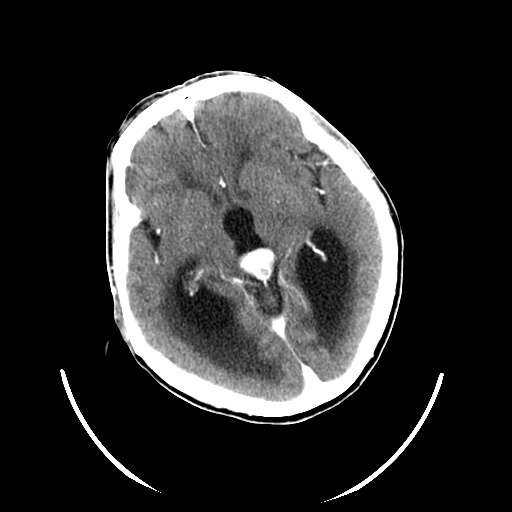

以下是引用zhangzhongshou在2007-10-8 19:16:00的发言:[br]大脑大静脉瘤[br]

以下是引用hhcckk在2007-10-9 10:03:00的发言:[br]galen';s静脉瘤又称大脑大静脉瘤,是由于动静脉短路,大量血流进入galen';s静脉(大脑大静脉),造成该静脉瘤样扩张所致,病理上典型的galen';s静脉瘤包括一明显扩张的囊状galen';s静脉和引流galen';s静脉的短路血管,,这些短路血管多来源于颈内动脉系统或基底动脉系统,多异常扩大、迂曲。巨大的galen';s静脉瘤可造成中脑压迫,导水管闭塞,引起梗阻性脑积水。[br]galen';s静脉瘤ct表现较典型,根据其部位、形态、增强前后表现及脑积水表现较易诊断。[br]支持张主任,此病人病灶强化明显,正常松果体增强后在病灶的后方可见,可以再做个mr,血管性的病灶在mr上有流空效应,增强后明显强化,诊断更有把握